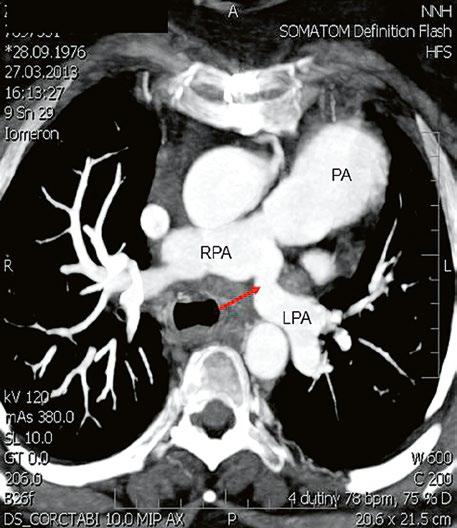

Supravalvární pulmonální stenóza a stenózy větví plicnice bývají součástí komplexních VSV (např. Fallotovy tetralogie) nebo syndromů (Williamsův syndrom, syndrom Noonanové, syndrom vrozené rubeoly, Alagillův syndrom aj.) (Obr. 45.39). Získané stenózy větví plicnice, ale i úplný uzávěr větve plicnice můžeme vidět po spojkových operacích podle BlalockaTaussigové (Obr. 45.40, Obr. 45.41). Pro zobrazení supravalvárních a periferních stenóz plicnice je optimální CT angiografie (Obr. 45.40, Obr. 45.41, Obr. 45.42, Obr. 45.43).

Obr. 45.40 CT angiografie, 8mm stenóza a deformace levé větve plicnice (šipka) po spojkové operaci podle BlalockaTaussigové v dětství LPA – levá větev plicnice, PA – kmen plicnice, RPA – pravá větev plicnice

Obr. 45.41 Uzávěr levé větve plicnice jako následek provedené spojky podle BlalockaTaussigové v dětství, CT angiografie